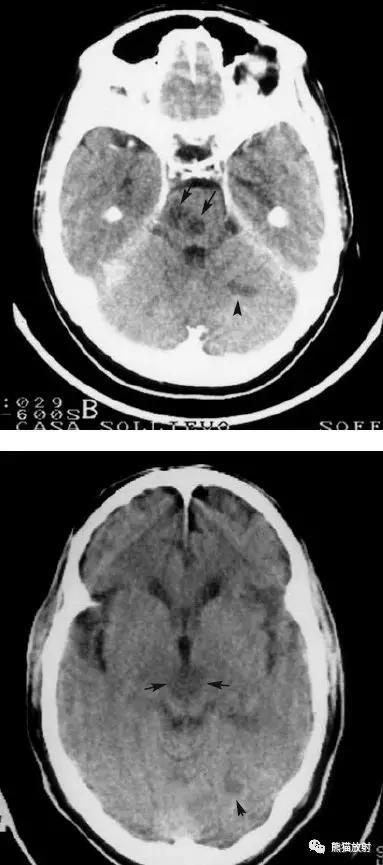

椎基底动脉区域的梗死:范围较广,非均质的低密度区域,累及脑干,小脑半球的前外侧以及颞叶的内后侧。

后颅窝梗死:脑桥、中脑、左小脑半球。

左侧及双侧丘脑梗死